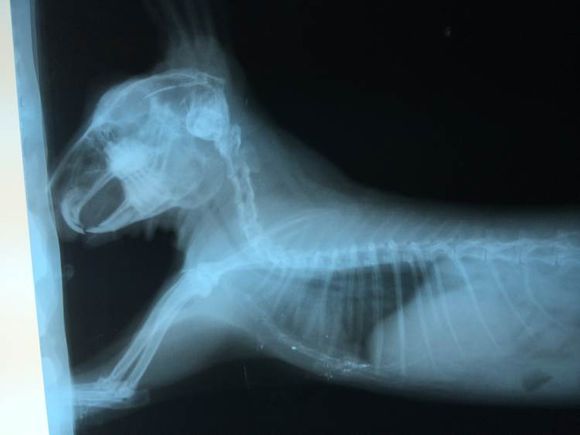

胃胀气的兔子活不过两年